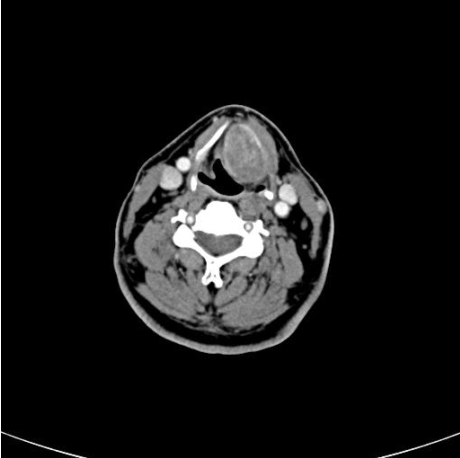

A 66-year-old male presented to our clinic with a two year history of progressively disabling dysphonia which had disrupted his career as a cantor. His physical examination was normal. Fiberoptic laryngoscopy revealed a bulging mass in the left paraglottic space extending to the vallecula and displacing the left vocal cord. A computed tomography (CT) scan was performed which demonstrated a 3.5 cm well delineated submucosal mass, located in the left paraglottic space and extending to the pre-epiglottic space and left vallecular region (Figures 1, 2). There was no evidence of cartilaginous destruction.

Figure 2: An axial post contrast CT scan showed a 3.5 cm mass that can be seen in the left paraglottic space. The mass was well circumscribed and no evidence of cartiliage destruction was seen.

Tumor presentation depends on the exact location of the mass. There are no specific clinical signs, and symptoms are usually progressive. When the origin is in the larynx, the most common symptoms are hoarseness, breathing difficulties, foreign body sensation, cough and throat clearing. [4] CT scan shows a submucosal dense homogeneous enhancement of the mass on post contrast studies. CT imaging is essential to rule out adjacent bony or cartilaginous involvement, which usually does not occur with solitary fibrous tumors. [2]